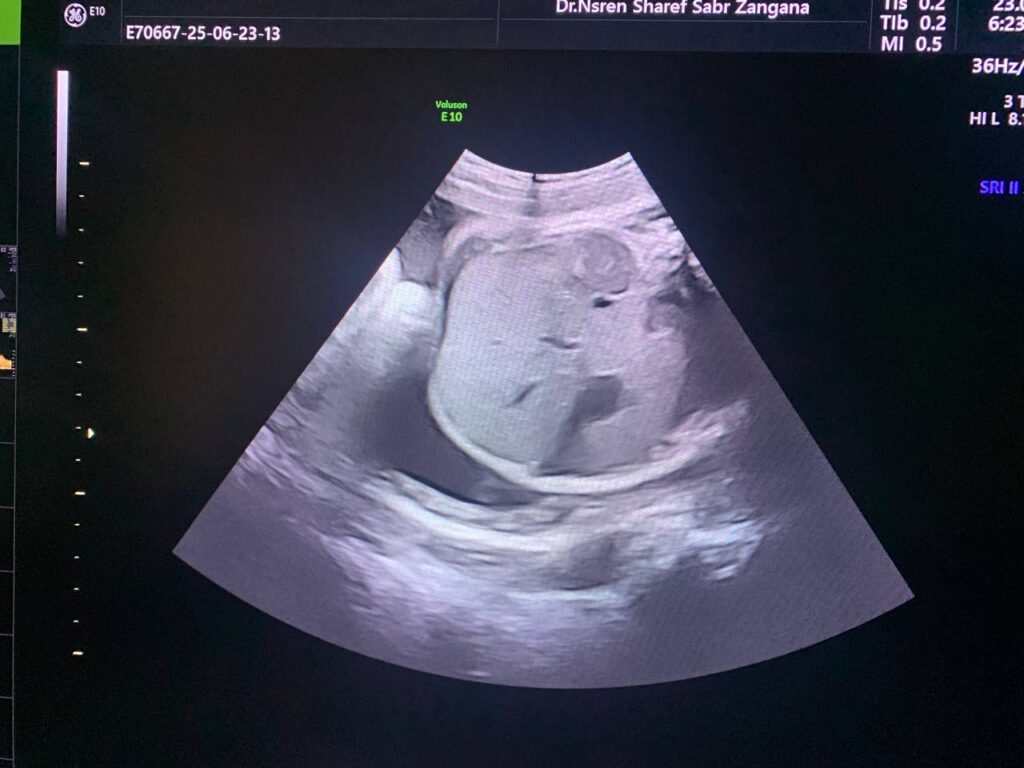

There’s focal Aneurysmal dilatation of the intrahepatic umbilical vein 10mm, normal ductus venosus flow seen, Also presence of small Blakes pouch cyst 4x5mm

At 29wk pregnancy

Focal aneurysm dilatation of the hepatic umbilical vein 16 in length , 12mm in diamter.

And with Increase in amount of liquor. Amniotic fluid index = 30cm AC =80% , Hepatomegally ?